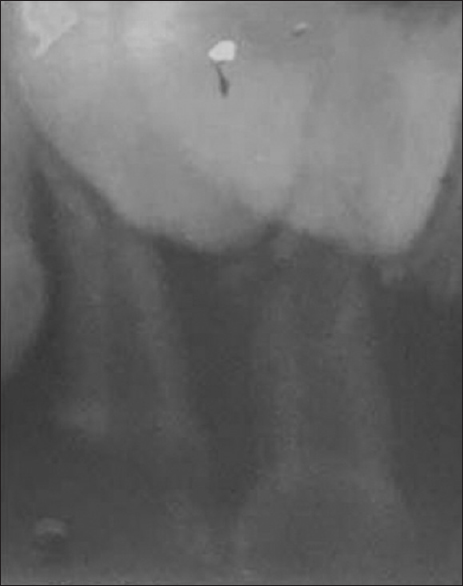

A 2½-year-old child patient reported to the Department of Pediatric and Preventive Dentistry with a chief complaint of broken teeth in the upper front region of the jaw. There was a loss of enamel and dentin on clinical examination due to caries in the left upper central and lateral incisors and dental caries with right central and lateral incisors [Figure 1]. Radiographic investigation revealed dental caries involving enamel, dentin, and pulp with loss of the tooth structure of the left upper central and lateral incisors. The present case report deliberates the use and clinical technique of biological restorations as possible and an efficient alternative treatment modality for rehabilitation of mutilated primary anterior teeth.

thumb

Figure 1: Preoperative radiograph